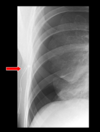

- example below: underinspired, basal lung marking are crowded together simulating infection